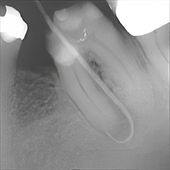

Hier sieht man den gleichen Zahn kurz vor der Abdrucknahme für eine Doppelkrone. Die beiden Wurzeln wurden behutsam voneinander getrennt (wir nennen das "Hemisektion"), um den Bereich zwischen den Wurzeln für die notwendige Zahnreinigung durch den Patienten zugänglich zu machen. Der stark erkrankte Zahn konnte durch diese schonenden, konservierenden Maßnahmen langfristig erhalten werden. Ein nach einer Extraktion notwendiger Zahnersatz in Form einer Brücke oder eines Implantates konnte erfolgreich vermieden werden.